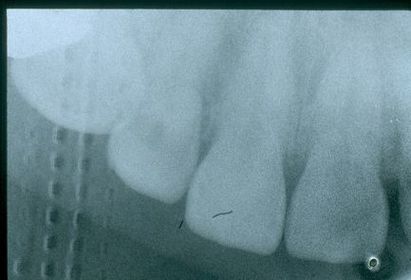

Radiogafía a revés Las lineas entrecortadas que se aprecian a la izquierda muestran que la laminilla de plomo se coloco hacia el área vestibular y no palatal.